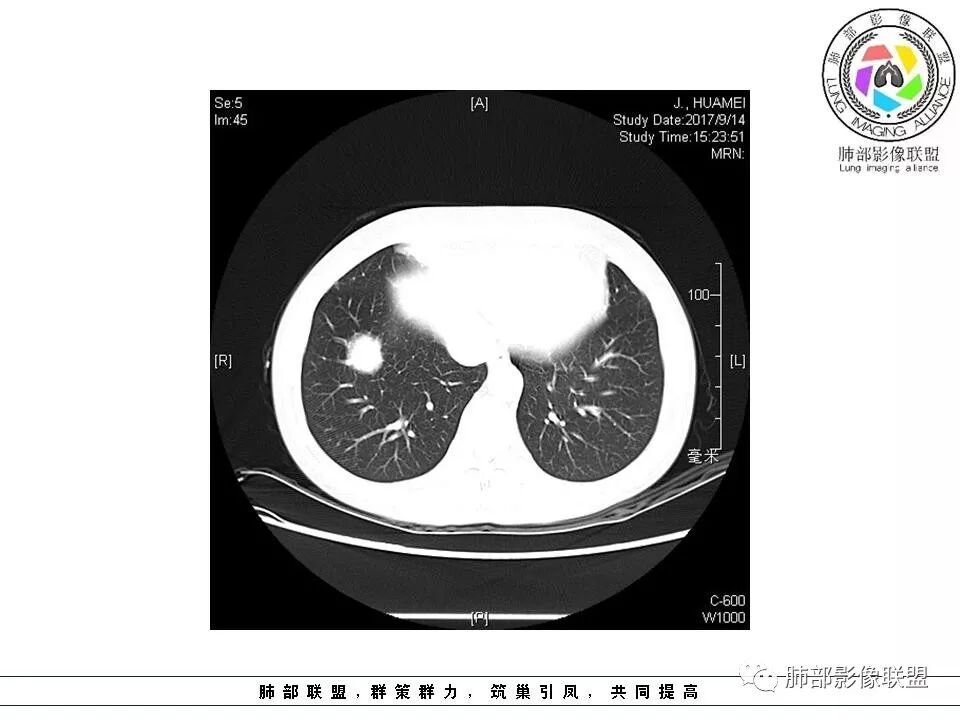

中年女性,体检发现,病史及化验无特殊。胸部CT右肺下叶前基底段见一类圆形结节,边界清楚,分叶不明显,边缘呈锯齿状改变,病灶内支气管穿行,无扩张及扭曲,增强扫描病灶明显均匀强化,内见穿行血管影,走形无扭曲。考虑粘膜相关性淋巴瘤可能。鉴别炎性假瘤、腺癌及小细胞癌。

边缘彭隆,还是考虑肿瘤,支气管通入,肺内原发,支气管自然穿行稍扩张,血管比较自然同行,漂浮征,增强后整个比较均匀无明显坏死,淋巴瘤首选。恶性应该没有问题,建议穿刺。

内部支气管走形非常自然,达远端稍扩张;内部血管穿行也非常自然

内部密度比较均匀,我们一般来说,首先良性肿瘤不支持,因为它里面的血管走形太自然了;然后就是炎性病变跟恶性肿瘤,但是它的边缘膨隆比较厉害,有些地方还毛刺,不是很清楚,倾向一个恶性病变

恶性的血管穿行自然,包括支气管稍扩张,最常见还是淋巴瘤,它强化比较均匀;

结果:粘膜相关淋巴组织结外边缘区B细胞淋巴瘤

支气管充气征伴或不伴支气管扩张:肿瘤细胞沿肺间质及支气管黏膜下组织浸润,支气管管壁未见明显破坏,管腔内未见肿瘤细胞充填,呈现充气支气管征;充气支气管走行自然,无扭曲、僵硬,内壁管腔光滑,支气管管壁见增厚并常有管腔的扩张,含气支气管可呈串珠样不均匀扩张,扩张明显处呈空腔样或皂泡样的囊状含气影;支气管扩张目前有两种意见:一是由于肿瘤组织起源于肺间质,肿瘤沿或跨越脏器解剖结构生长,原有解剖结构残留,周围增生的纤维结缔组织牵拉导致支气管扩张;二肿瘤侵犯支气管粘膜下植物神经丛致平滑肌张力丧失;而这类支气管扩张在肿瘤治疗后有时可消失。

血管造影征:肿瘤组织浸润引起间质增厚、肺泡壁破坏、肺泡腔充填,而周围充盈血管走行自然,未受肿瘤侵犯。

病例小结:如临床症状轻,肺内多发或单发的结节、肿块及实变,沿血管支气管束、肺间质及胸膜下分布,密度及强化均匀,伴支气管充气征,支气管可扩张,血管造影征,周围有间质性改变,有炎性特点(平直、收缩、周围晕征及树芽),又有肿瘤特点,纵膈及肺门未见肿大淋巴结,没有明显胸膜增厚及胸腔积液,尤其是影像相对稳定,都要想到这个肺黏膜相关淋巴组织淋巴瘤的可能;回顾性分析本病例,还是很符合MALT淋巴瘤影像表现;但是这个患者的NSE轻度升高,使很多群友都想到了小细胞肺癌、类癌的这些神经内分泌肿瘤;神经元特异性烯醇(NSE),是小细胞肺癌、类癌还有其他神经内分泌肿瘤的特异性和敏感性较高的肿瘤标志物,正常值为0-16ng/ml,但是此患者NSE值为17.1ng/ml,为轻度升高;如果在小细胞肿瘤和神经内分泌肿瘤中,NSE是成数十倍的增高,恶性肿瘤的可能性就比较大。如果是轻度升高,诊断神经内分泌肿瘤意义不大,而且里面的支气管充气征伴扩张都不大符合小细胞肺癌和类癌的影像表现。小细胞癌常进展迅速,转移早。